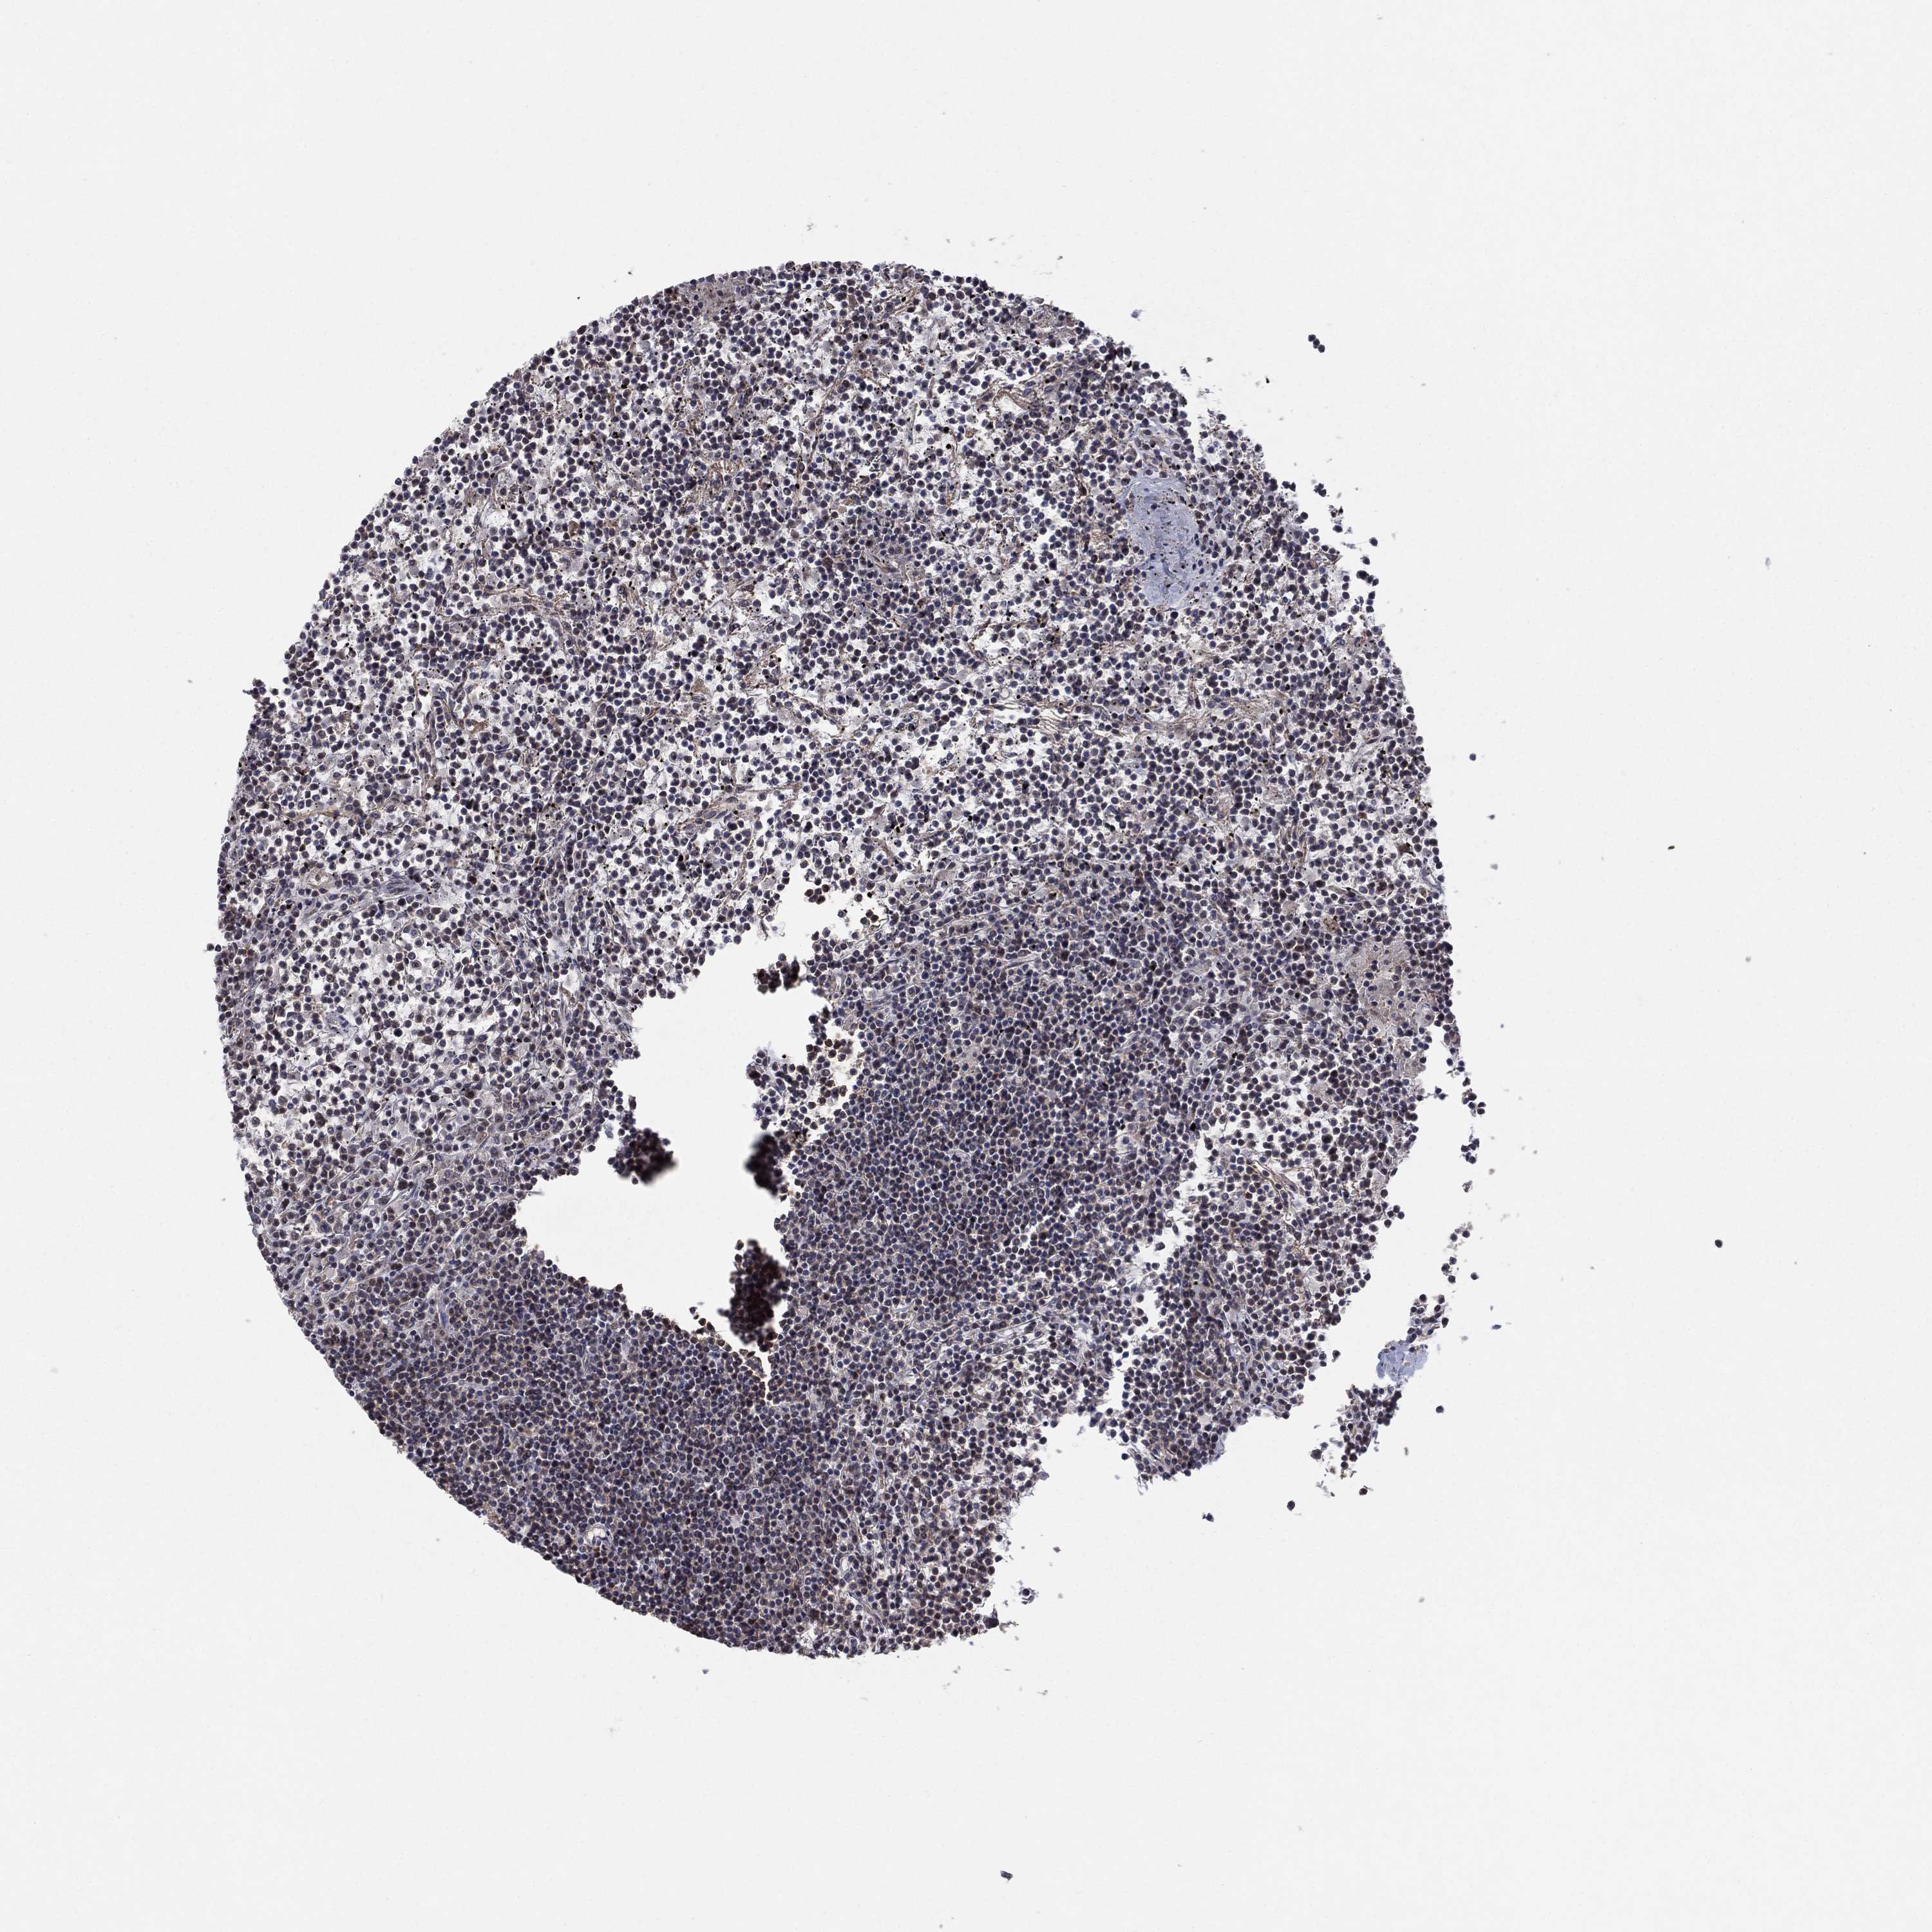

CANCER LYMPHOMA Show tissue menu

LYMPHOMA - Protein expressioni

A mouse-over function shows sample information and annotation data. Click on an image to view it in a full screen mode. Samples can be filtered based on level of antibody staining by selecting one or several of the following categories: high, medium, low and not detected. The assay and annotation is described here.

Each image is clickable and will lead to virtual microscopy that enables deeper exploration of all samples and also displays staining intensity scores, fraction scores and subcellular localization as well as patient and tissue information for each sample.

Antibody HPA076275

Staining

High

Medium

Low

Not detected

Intensity

Strong

Moderate

Weak

Negative

Quantity

>75%

75%-25%

<25%

None

Location

Nuclear

Cytoplasmic/membranous

Cytoplasmic/membranous,nuclear

Malignant lymphoma, non-Hodgkin's type, Low grade

Malignant lymphoma, non-Hodgkin's type, High grade

Hodgkin's disease, NOS